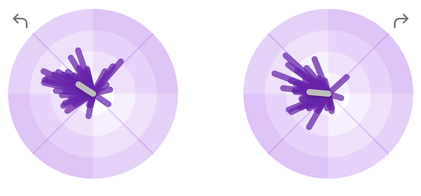

Objektive Ganganalyse: KI-Diagnostik mit Sleip